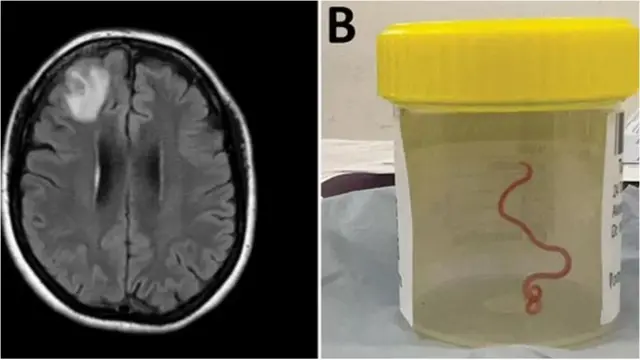

Мээден тирүү курт табылды

Дүйнөдө биринчи жолу окумуштуулар австралиялык аялдын мээсинен 8 см (3 дюйм) тирүү куртту алып салышты.

"Жип сымал түзүлүш" өткөн жылы Канберрада операция учурунда бейтаптын жабыркаган маңдай бөлүгүнөн алынган, бирок операция тууралуу отчет быйыл гана жарыяланды. "Албетте, бул биз күткөндөй болгон жок. Баары таң калышты", - деди операциялык хирург доктор Хари Прия Банди.

64 жаштагы аял бир нече ай бою ашказан оорусу, жөтөл жана түнкү тердөө сыяктуу симптомдорду башынан өткөрүп, унутчаактык менен депрессияга тушуккан. Ал 2021-жылдын январь айынын аягында ооруканага жаткырылган жана кийин сканерлөө "мээнин оң фронталдык бөлүгүндөгү атиптик жараканы" көрсөткөн.

Бирок анын абалынын чыныгы себеби 2022-жылдын июнь айында, биопсия учурунда, доктор Бандинин бычагы аркылуу гана аныкталган. Дарыгерлердин айтымында, кызыл мите анын мээсинде эки айга чейин жашай алмак. "Анын иши личинкалардын адамдын мээсине басып киришинин жана өнүгүшүнүн биринчи учуру болуп саналат" - деп белгилешти изилдөөчүлөр бул окуяны кабарлаган Emerging Infectious Diseases журналында. Окумуштуулар бул окуя жаныбарлардан адамдарга жугуучу оорулардын жана инфекциялардын кооптуулугун ачык көрсөтөт деп билдирди. (МА)